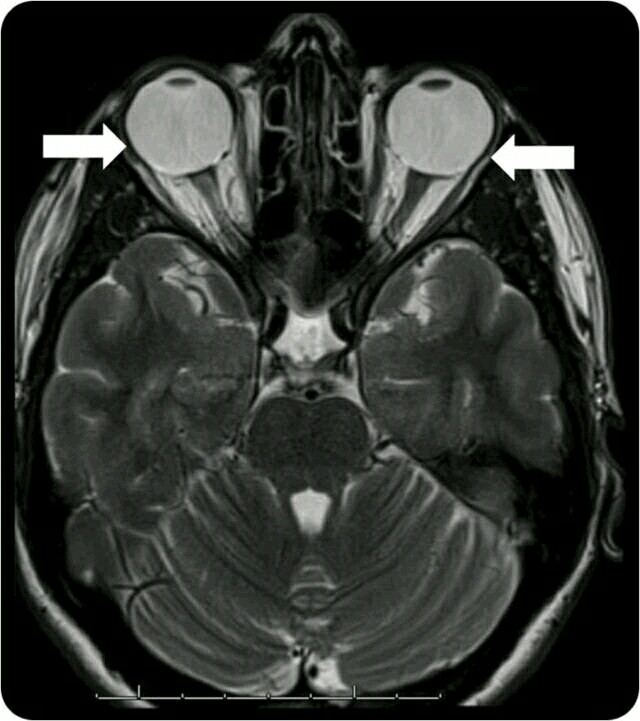

患者女性,30 岁,近视(8 屈光度)伴进展性双眼水平复视 1 年余。既往有慢性偏头痛病史,余病史无特殊。眼球运动检查示共同性内斜视(20 屈光度),右上斜眼(2 屈光度)。MRI(图 1、2)可见重眼综合征的特征表现:眼球后部向颞上脱垂,外直肌退化--上直肌、外直肌下移。外展受限可能是第六对颅神经麻痹所致。该患者经三棱镜治疗后症状明显改善。 图 1. 眼眶 MRI 显示眼球拉长和上外侧移位(图中箭头所示) 图 2. 上直肌拉伸--外直肌带(箭头所示)和外直肌下移,左侧较右侧重